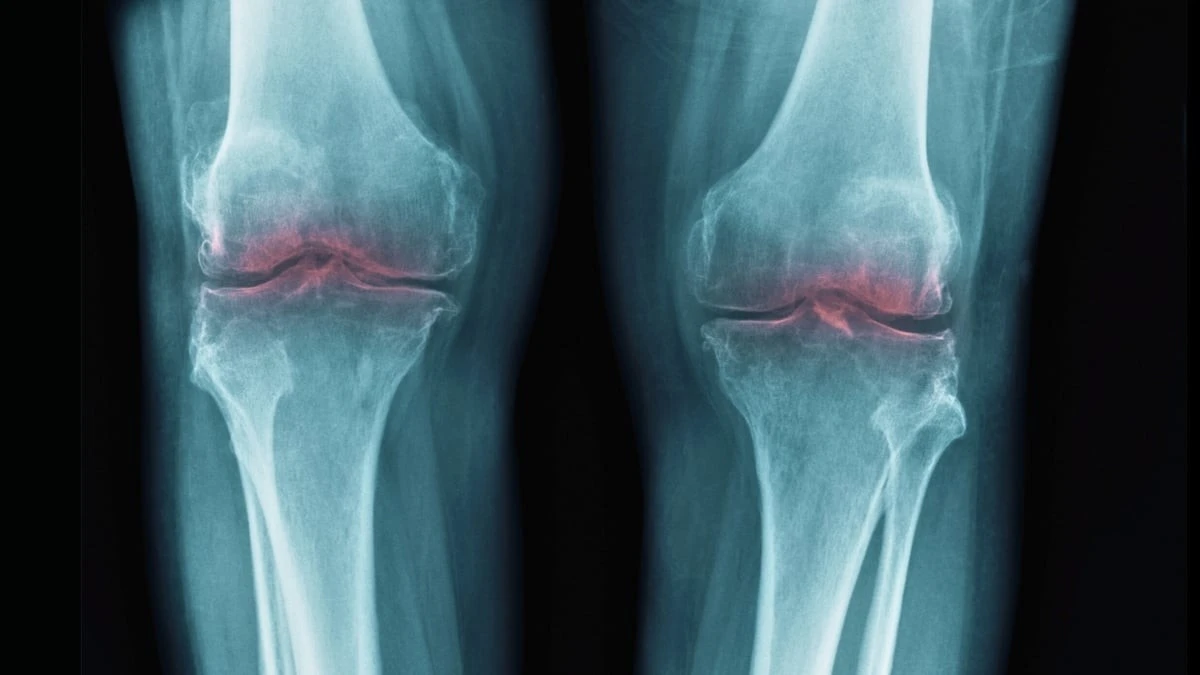

Možná to znáte taky – ranní ztuhlost v kolenou nebo nepříjemné loupání v kyčli při každém schodu. Většině z nás lékaři roky tvrdili, že chrupavka se prostě opotřebuje a jedinou konečnou stanicí je totální endoprotéza. Nová studie však ukazuje, že naše tělo má schopnost opravy stále v sobě, jen ji někdo musí umět aktivovat.

- Viditelné výsledky: U testovaných subjektů došlo k reálnému zesílení chrupavky a návratu stability při chůzi.

Vědci jsou optimističtí. Klinické testy by mohly začít už během příštího roku a půl. Cílem není jen potlačit bolest růžovou pilulkou, ale skutečně zvrátit poškození, které už vzniklo. Představa, že se v šedesáti vyhnete výměně kolene díky injekci, která „probudí“ vaši chrupavku, už není sci-fi.